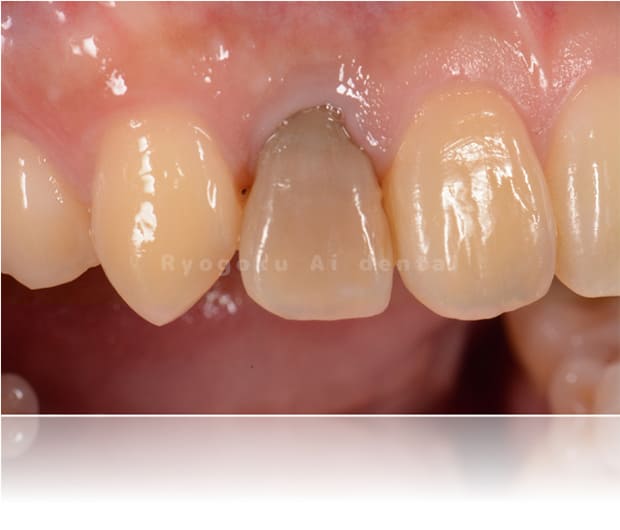

Case03

-

- 原因

- 失活による歯牙変色

- 治療内容

- ブリーチング+マイクロエンド+ダイレクトボンディング

- 治療費用

- 198,000円(ブリーチング55,000円+マイクロエンド77,000円+ダイレクトボンディング66,000円)

前歯が黒いのが気になるとのことでご来院された患者様です。根の状態も悪かったためマイクロスコープ下で根管治療を行い、ブリーチングの後にダイレクトボンディングで形態修正を行いました。